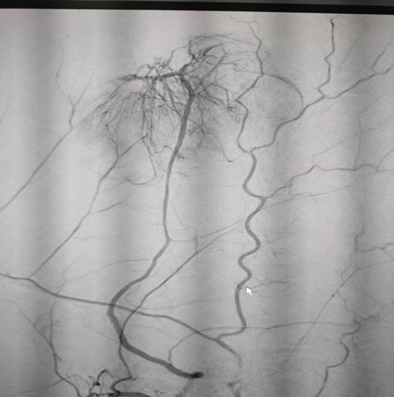

A-45-year-old right-handed lady with no significant past medical history presented with left sided hemicranial headache and a single secondary generalized convulsion. Clinical examination was normal with no other neurological deficit. Funduscopy revealed no papilledema. MRI brain without contrast identified a large left frontal extra-axial space occupying lesion with a dural tail suggestive of a meningioma with mass effect (Figure 1). Routine biochemical and haematological parameters were normal. Levetiracetam was started for seizure prophylaxis. Preoperative embolization of the tumor was planned followed by resection after 48 hours. Endovascular embolization was performed under conscious sedation. Vascular access was obtained via standard left femoral artery approach. Diagnostic angiography revealed tumoral blood supply from left middle meningeal artery and right ophthalmic artery (Figure 2). Super-selective microcatheterization of the left middle meningeal artery was achieved and tumorous feeders from ophthalmic artery were not embolized (Figure 3). Tumor embolization was achieved with polyvinyl alcohol particles (150 to 250 um). The patient was started on intravenous dexamethasone. Embolization of middle meningeal artery was followed by craniotomy after 48 hours. Simpson grade I resection of the tumor was achieved with around 300 ml periprocedural blood loss. There was no new onset neurological deficit following surgery. Post-operative hospital course was uneventful, and she was discharged home after 4 days. Histopathological examination revealed a WHO grade I meningioma. Review of medical literature was carried out to determine the optimal interval of resection following embolization of a large meningioma.

Figure 1 Large left frontal meningioma with mass effect.